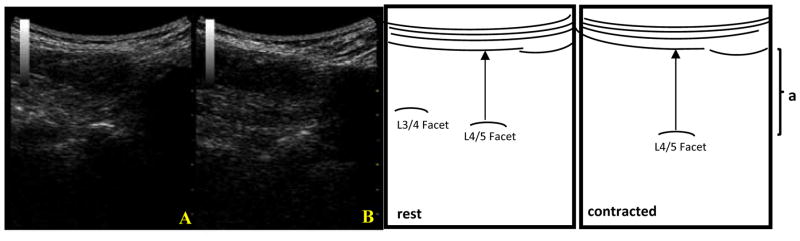

FIGURE 2.

On the left are ultrasound images of the multifidus obtained via parasagittal imaging at rest (A) and during a straight leg raise (B) in a younger adult. On the right are anatomical diagrams showing the standard measurement technique for multifidus thickness, where (a) represents multifidus muscle. The standard measurement is taken from the facet joint to the last dark pixel before the muscle’s fascial line.